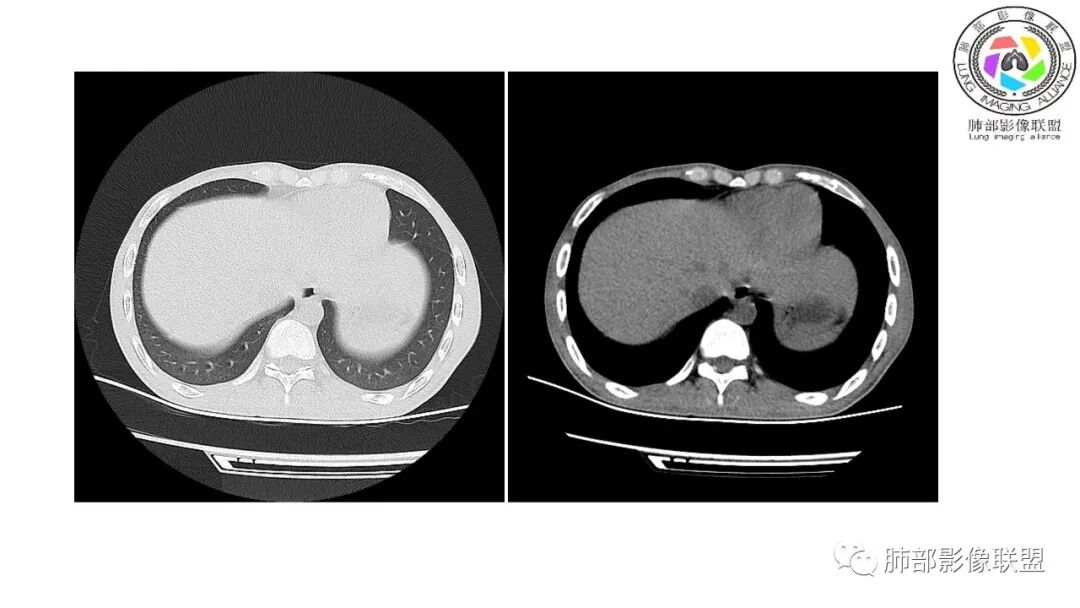

影像与临床:1.青年男性,HlV阳性,颜面部皮疹(未提供皮疹图像)、发热(高热),实验室CRP、PCT高,T-Spot阴性。2.右肺下叶空洞结节,壁厚不均,边界清楚,其内线状影,未见液平及钙化,未见卫星灶,纵隔淋巴结增大,双侧腋窝见增大淋巴结。心腔内低密度提示贫血可能。肝脾影增大,未见结节影及块影。腹膜后见多发增大淋巴结。

综合分析:本例肺部影像学改变并不具有特征性,空洞性病灶须与多种疾病鉴别,但年轻HIV阳性患者,高热,皮疹,肝脾增大,纵隔、腋窝、腹膜后见多发增大淋巴结等都强烈提示马尔尼菲篮状菌感染的可能性。